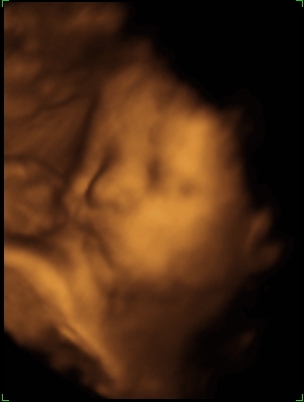

A doki szerint pufók kislány